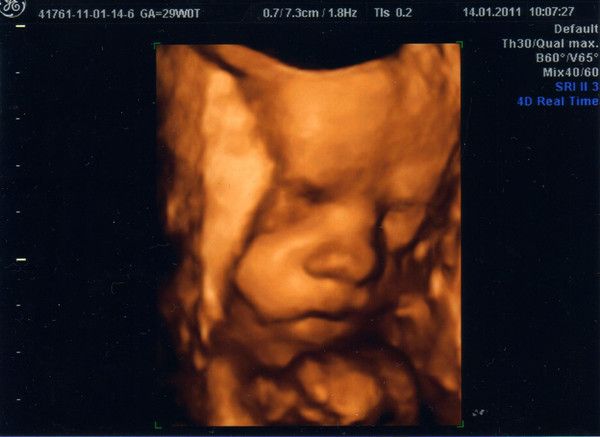

2.Bild_samulu_ET01042010

08.09.2010

Krümel hat schon eine Größe (SSL) von 37mm in SSW10+5T, innerhalb von 14 Tagen ist er doppelt so groß geworden.